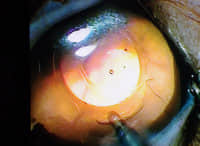

术前右眼 术前左眼

术后左眼 术后左眼

术后右眼

今天的第三台手术依然是临床上常见的患白内障的品种,一只年仅2岁多的泰迪犬,一年多前右眼就出现了白内障,近半年右眼也出现了同样的问题,主人经介绍找到我进行双眼的白内障手术。 由于病程左长,我担心其视网膜的功能受到影响,但视网膜的检查一切都还正常,虽然视网膜检查的数值略低,但并不影响手术的进行。手术在下午两点准时开始,尽管因为病程过长造成了晶状体的液化,但手术还是非常顺利完成,并且双眼都植入了人工晶体。目前各项指标都非常正常。